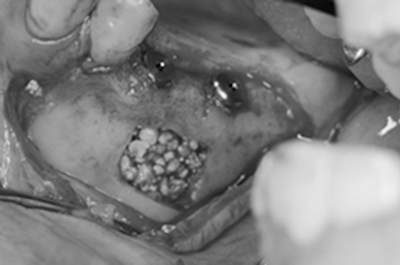

手術中。埋入と同時にサイナスリフトを行いました。